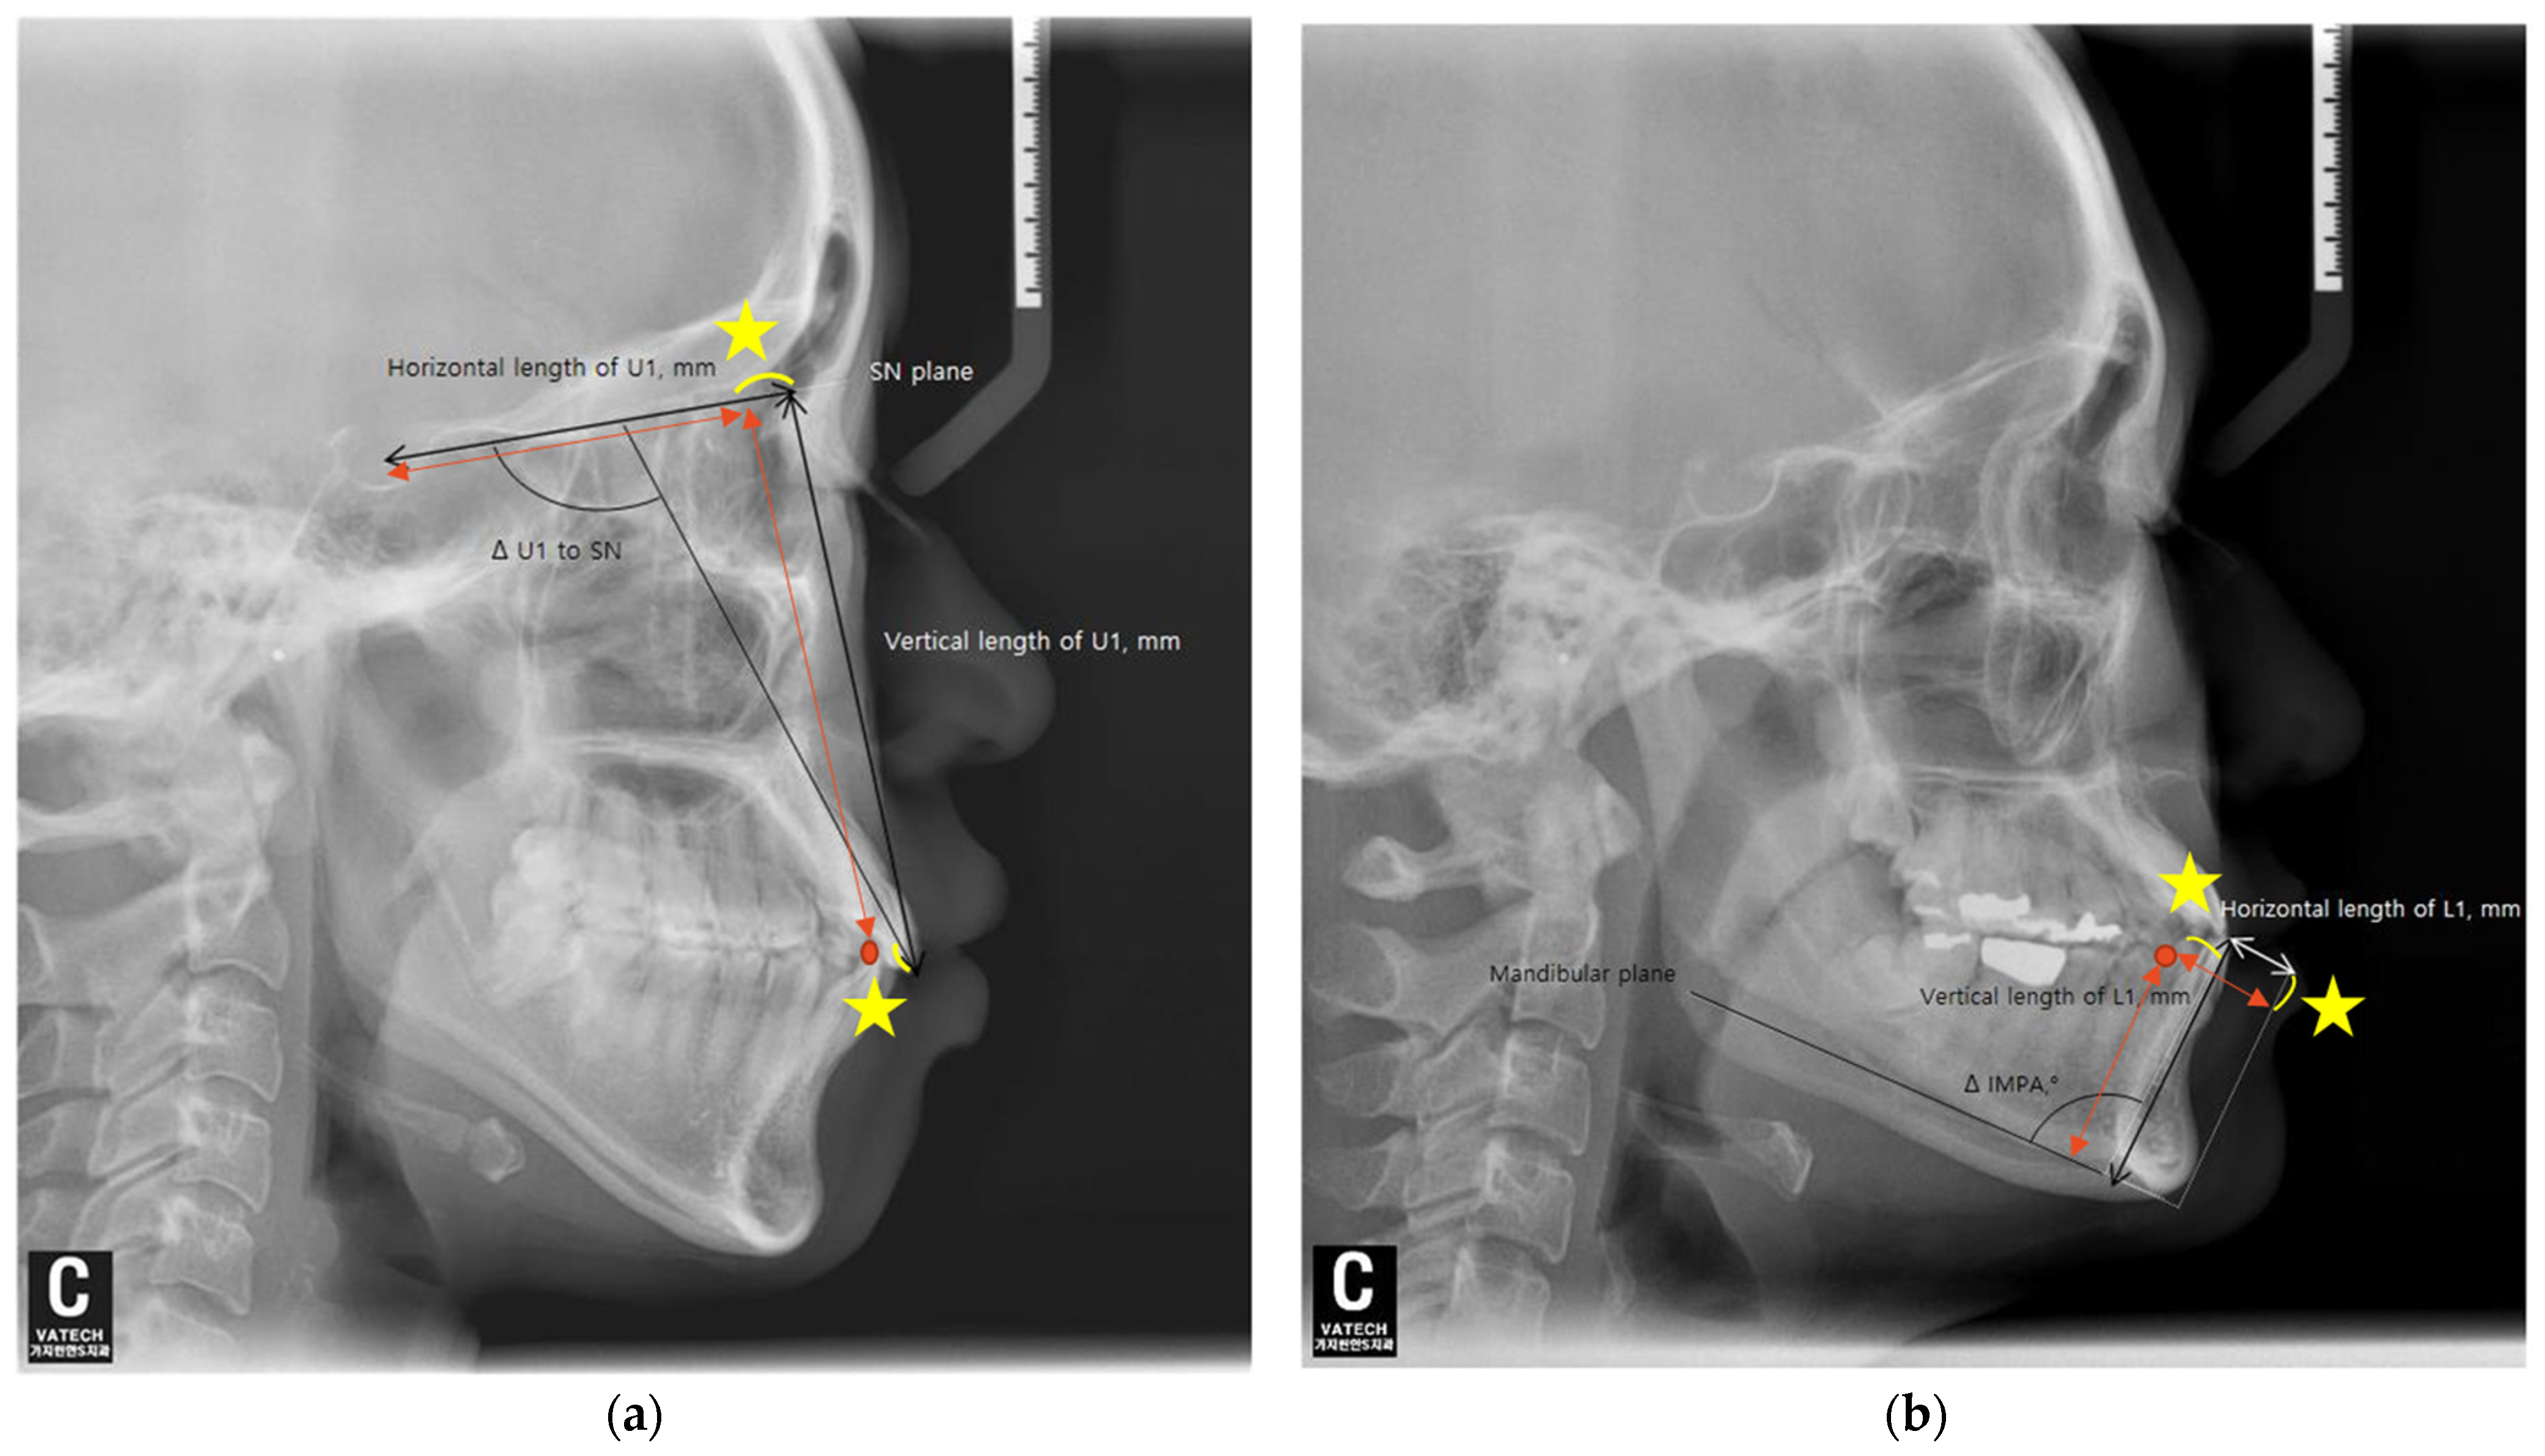

The angular and anteroposterior, as well as vertical, changes in the maxillary and mandibular central incisors before and after orthodontic treatment were measured using lateral cephalometric radiographs. Each radiograph was taken in a natural head position. Additionally, all subjects were instructed to stand still, hold their breath, swallow briefly before imaging, and refrain from swallowing while the radiographs were being taken. For the maxillary central incisors, the angular change was assessed by measuring the difference in the angle between the upper incisor and the SN plane (ΔU1 to SN), and for the mandibular central incisors, the difference in the incisor mandibular plane angle (ΔIMPA) was measured relative to the mandibular plane before and after orthodontic treatment.

The horizontal movement of the maxillary central incisors was measured as calculating the change in the distance between the perpendicular line drawn from the tip of the maxillary central incisor crown to the SN plane and the distance from this point to the Sella (S) (ΔTH = TH2 − TH1). The vertical movement of the maxillary central incisors was calculated by measuring the change in the perpendicular distance from the tip of the maxillary central incisor crown to the SN plane (ΔTV = TV2 − TV1) (Figure 2a).

For the mandibular central incisors, the horizontal movement was assessed by measuring the change in the straight-line distance between the tip of the mandibular central incisor crown and the perpendicular line drawn from the mandibular plane to the Pogonion (ΔTH = TH2 − TH1). The vertical movement was calculated by measuring the change in the perpendicular distance from the tip of the mandibular central incisor crown to the mandibular plane (ΔTV = TV2 − TV1) (Figure 2b).

Figure 2. Lateral cephalograms show measurements of tooth movement. (a) SN, Sella–Nasion; U1, the maxillary central incisor; Δ U1 to SN refer to the changes in measurements between before (T1) and after (T2) treatment (Δ = T2 − T1). (b) L1, the mandibular central incisor; IMPA, incisor mandibular plane angle. Δ IMPA refers to the changes in measurements between before (T1) and after (T2) treatment (Δ = T2 − T1).